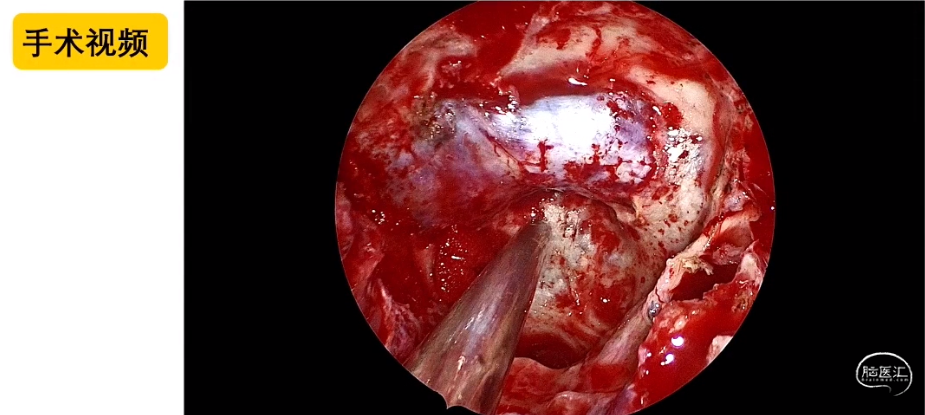

刘庆教授:经鼻内镜技术在复杂颅底肿瘤手术中的应用与思考